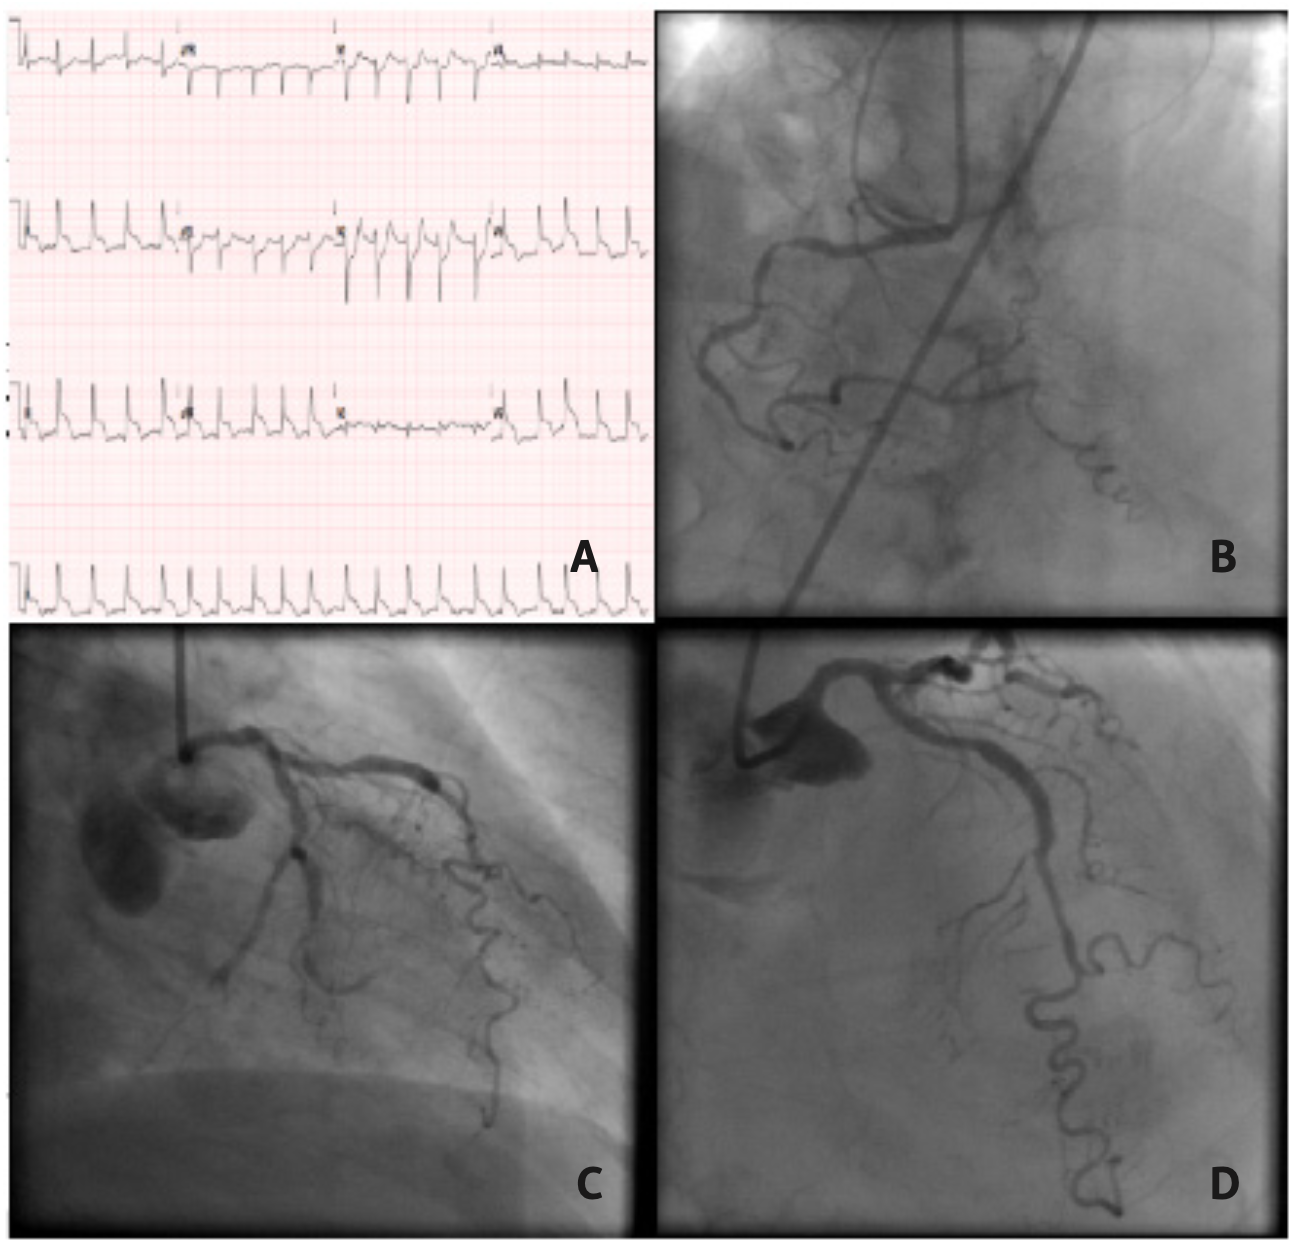

A 93-year-old female patient with previous history of hypertension, atrial fibrillation, and ischemic stroke presented at the emergency department due to epigastric pain, malaise, sweating, and somnolence with 24 hours of evolution. Clinical examination revealed irregular cardiac rhythm and impaired peripheral perfusion. Blood pressure was 130/87 mm Hg and heart rate was 114 bpm. Inferior-lateral and right ventricular ST-segment elevation were present in the electrocardiogram. Bedside echocardiogram showed a severe ventricular dysfunction and pericardial effusion with an adherent clot, without identifying the perforation site.

Fluid replacement and vasopressor were initiated as blood pressure began to drop. Orotracheal intubation was performed due to respiratory failure. The patient was transferred to the catheterization laboratory for emergency cardiac catheterization. Coronary angiography showed a thrombotic occlusion of the distal left circumflex artery (LCX) and proximal marginal branch. The proximal left anterior descending artery (LAD) and right coronary artery (RCA) had severe lesions (Figure 1). Due to hemodynamic deterioration, pericardiocentesis was performed with a pigtail catheter (Figure 2) with transient improvement, but failed to empty the pericardium due to continuous blood filling. Hemodynamics continued to deteriorate and several cardiac arrests developed, with transient returns of spontaneous circulation. After considering the condition irreversible, we injected contrast in the pericardium to confirm diagnosis, showing 2 perforations in the left ventricular free wall (Video 1). The patients died minutes later.